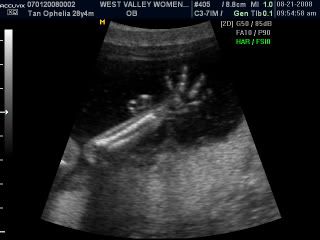

His tiny skeletal hands!